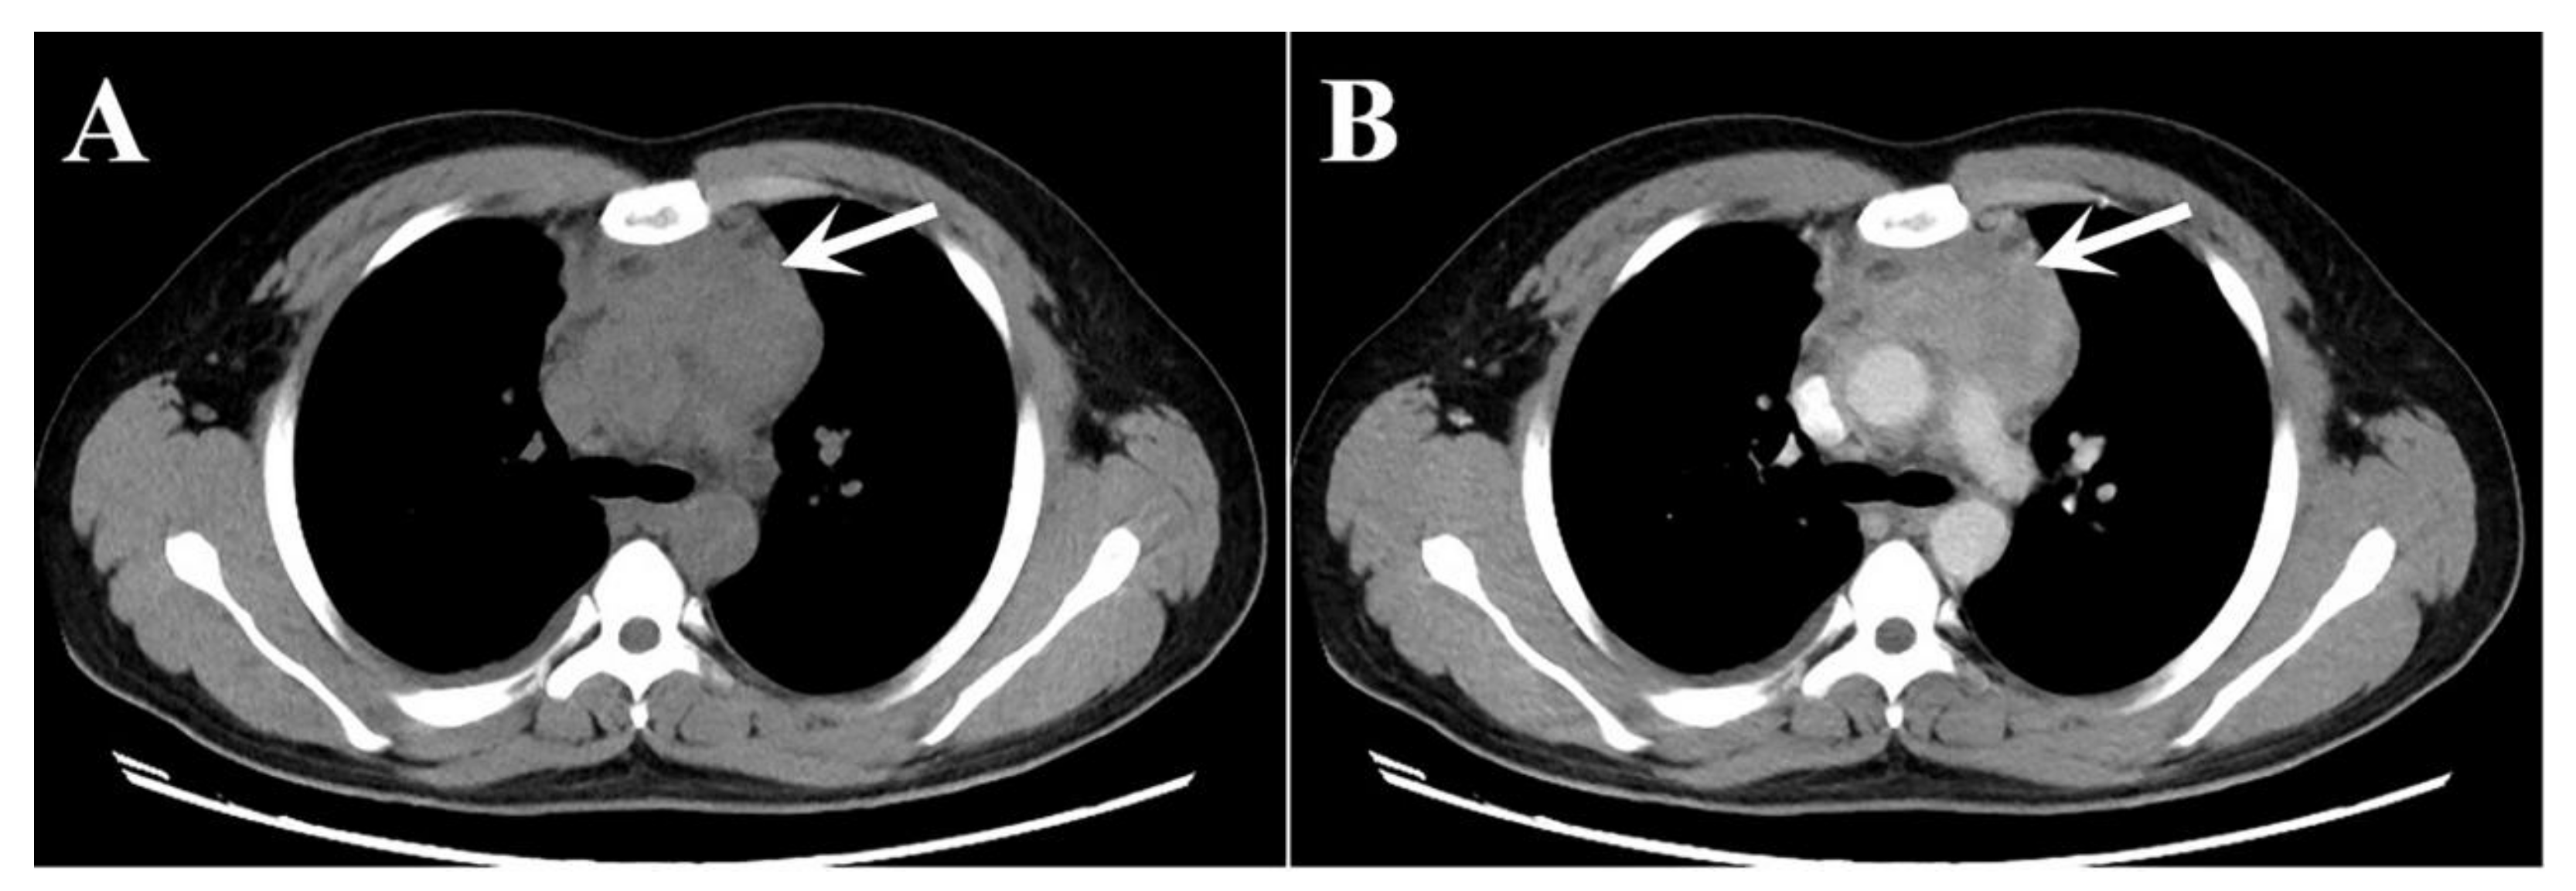

2. Case Presentation